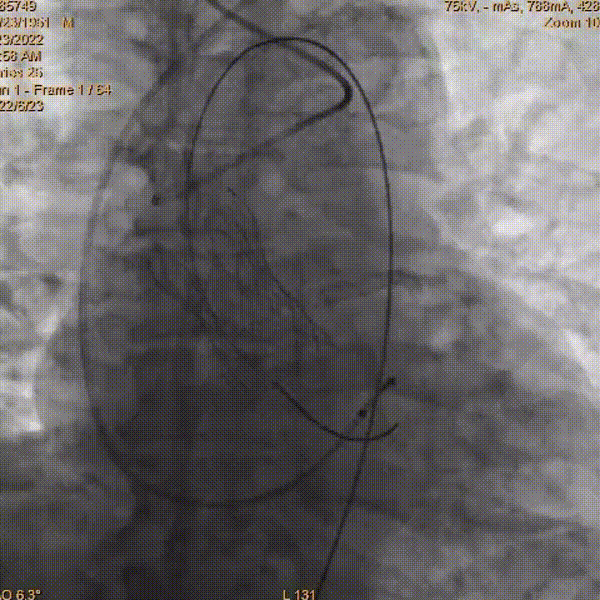

术中影像:

主动脉根部造影

AV26mm瓣膜释放至工作位